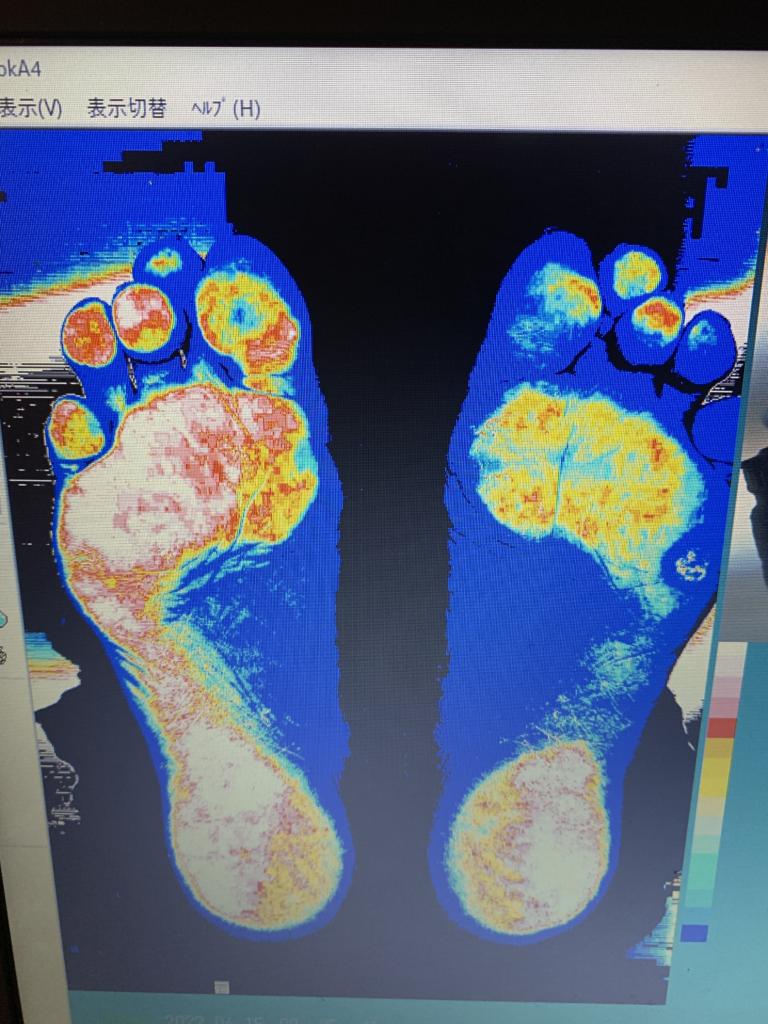

Beforeの足底圧

Afterの足底圧